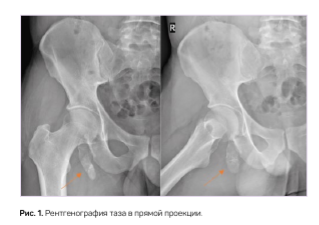

При дообследовании на КТ и МРТ области таза кзади от правой седалищной кости с распространением по квадратной мышце бедра отмечаются два фрагмента круглой формы, за которыми располагается протяженный фрагмент с наличием кортикального слоя, общими размерами 20 х 17 х 67 мм, с линией конкрестенции в дистальных отделах с более мелким фрагментом (рис. 2). Данные фрагменты не имели связи с костями таза, располагались свободно в мышце. Отека, увеличения объема мышц на этом уровне отмечено не было (рис. 3). После изучения литературы и сопоставления данных лучевого исследования выставлено заключение «тазовый палец». Дальнейшее лечение не проводилось, так как пациенту данная «находка» дискомфорт не причиняла.